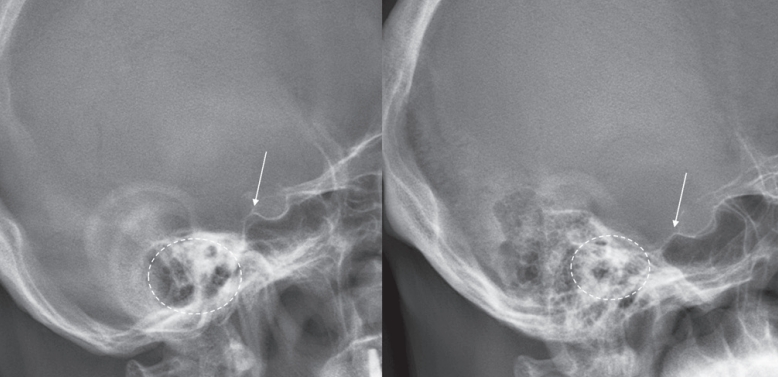

1,2) 외이도(external auditory meatus, EAM)는 MNI의 근사값으로서 두개 중심의 기준점으로 널리 사용되어 왔으나, 방사선 영상에서의 명확성과 일관성이 저하되는 경우가 많다. 이는 주로 확산된 유양돌기 공기세포(mastoid air cells)와 측면 영상에서의 중복(double contour) 현상으로 인해 발생한다(

Fig. 1). 반면, 터기 안장(sella turcica) 은 단일 중심 구조로서 대부분의 경우에서 주변 해부학적 구조에 의해 가려지지 않고 명확히 확인 가능하다. 아직까지 방사선 영상에서의 외이도의 신뢰도에 대해 평가한 연구는 많지 않다. 본 연구에서는 외이도의 방사선학적 가시성과 MNI와의 공간적 관계를 분석함으로써, 두개 중심의 기준점으로서의 신뢰성을 검증하고, 이를 터기 안장과 비교하고자 한다.

Fig. 1.수술 전 전신 척추 방사선 영상에서 촬영된 다양한 환자의 두부 영상 예시들이다. 흰색 화살표는 터기 안장(sella turcica)의 후방 경각을, 점선 원은 외이도(external auditort meatus)를 각각 나타낸다. 대부분의 환자에서 터기 안장은 명확하고 단일한 구조로 관찰되는 반면, 외이도는 불명확하거나 이중으로 나타내는 경우가 많다.